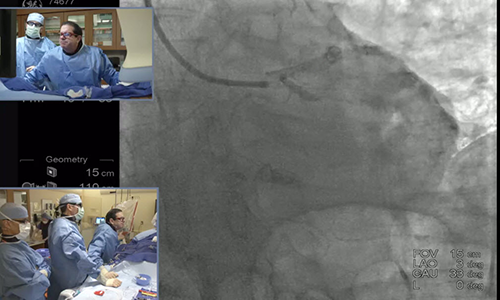

Complex PCI Case with Dr. Paul Teirstein

Dr. Teirstein expertly approaches a previously failed PCI in a lesion with heavy calcification requiring the use of rotational atherectomy, advanced access techniques, and physiological significance measurement.